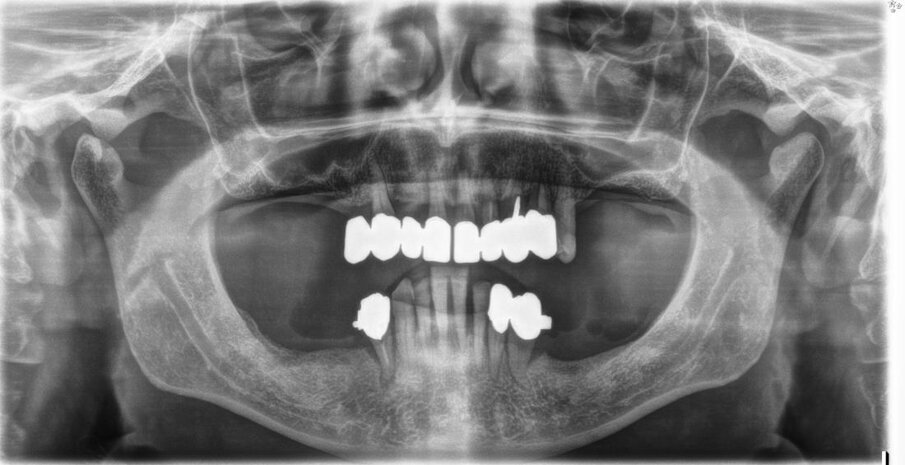

Si effettua solo una ortopantomografia, nessun sondaggio, nessuna valutazione parodontale. Si estraggono i denti, si inseriscono gli impianti, ma… non ci stanno! Tra mille problemi tecnici, diversi operatori e molteplici rifacimenti l’implanto-protesi viene finalizzata dopo oltre 3 anni, ma determina problemi masticatori. Alcune corone si rompono, non è funzionale (il paziente non si riesce a mangiare), fa male, ma soprattutto non piace all’anziano signore.

Inoltre, la protesi traumatizza con le parti metalliche i tessuti molli e la lingua, le corone sono inclinate in senso vestibolare e non occludono alla perfezione. L’overjet è ampio ed è presente un morso aperto anteriore, con trauma sui posteriori. Si vedono i colletti metallici degli impianti, metallo compare negli spazi interprossimali (corone ed impianti non sono in linea)(Figg. 2-4).